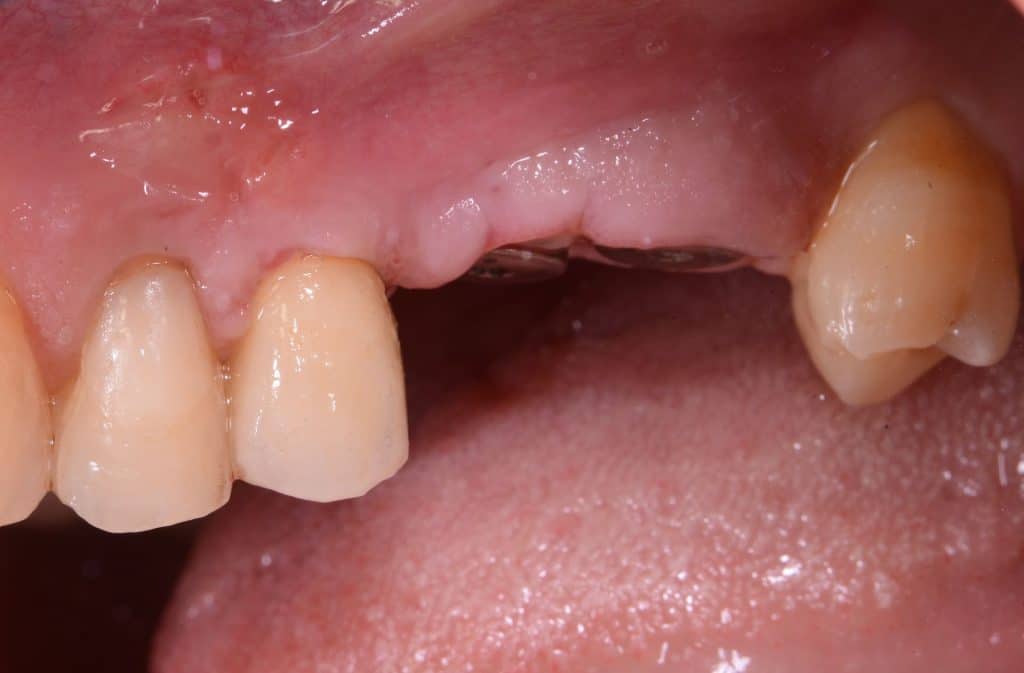

operating area, occlusal view

operating area, lateral view